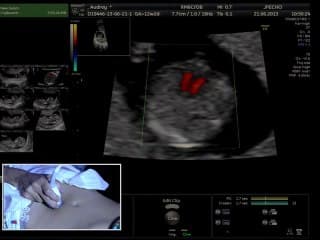

La médiathèque du Collège Français d'Échographie Fœtale (CFEF) constitue l'une des plus importantes collections de ressources vidéo dédiées à l'échographie fœtale en France. Avec plus de 3 261 vidéos, elle couvre l'ensemble des thématiques liées à la pratique échographique prénatale.

Vous y trouverez des conférences présentées lors des congrès nationaux et internationaux, des cours magistraux dispensés par des experts reconnus, des démonstrations pratiques sur des cas cliniques réels, ainsi que des podcasts et tables rondes sur les dernières avancées de la spécialité.